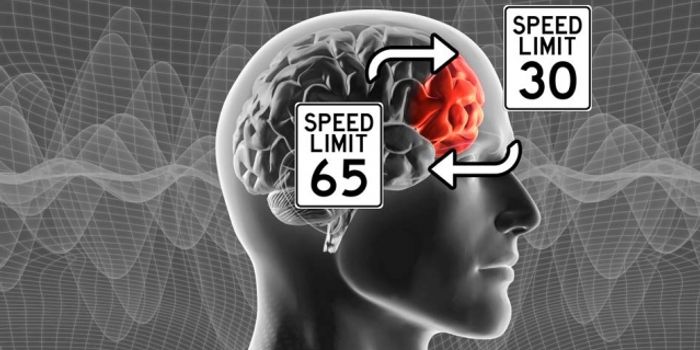

SEP 19, 2019NeuroscienceResearchers from the University of California have found a low-cost, non-invasive method to aid in diagnosing Alzheimer& ...